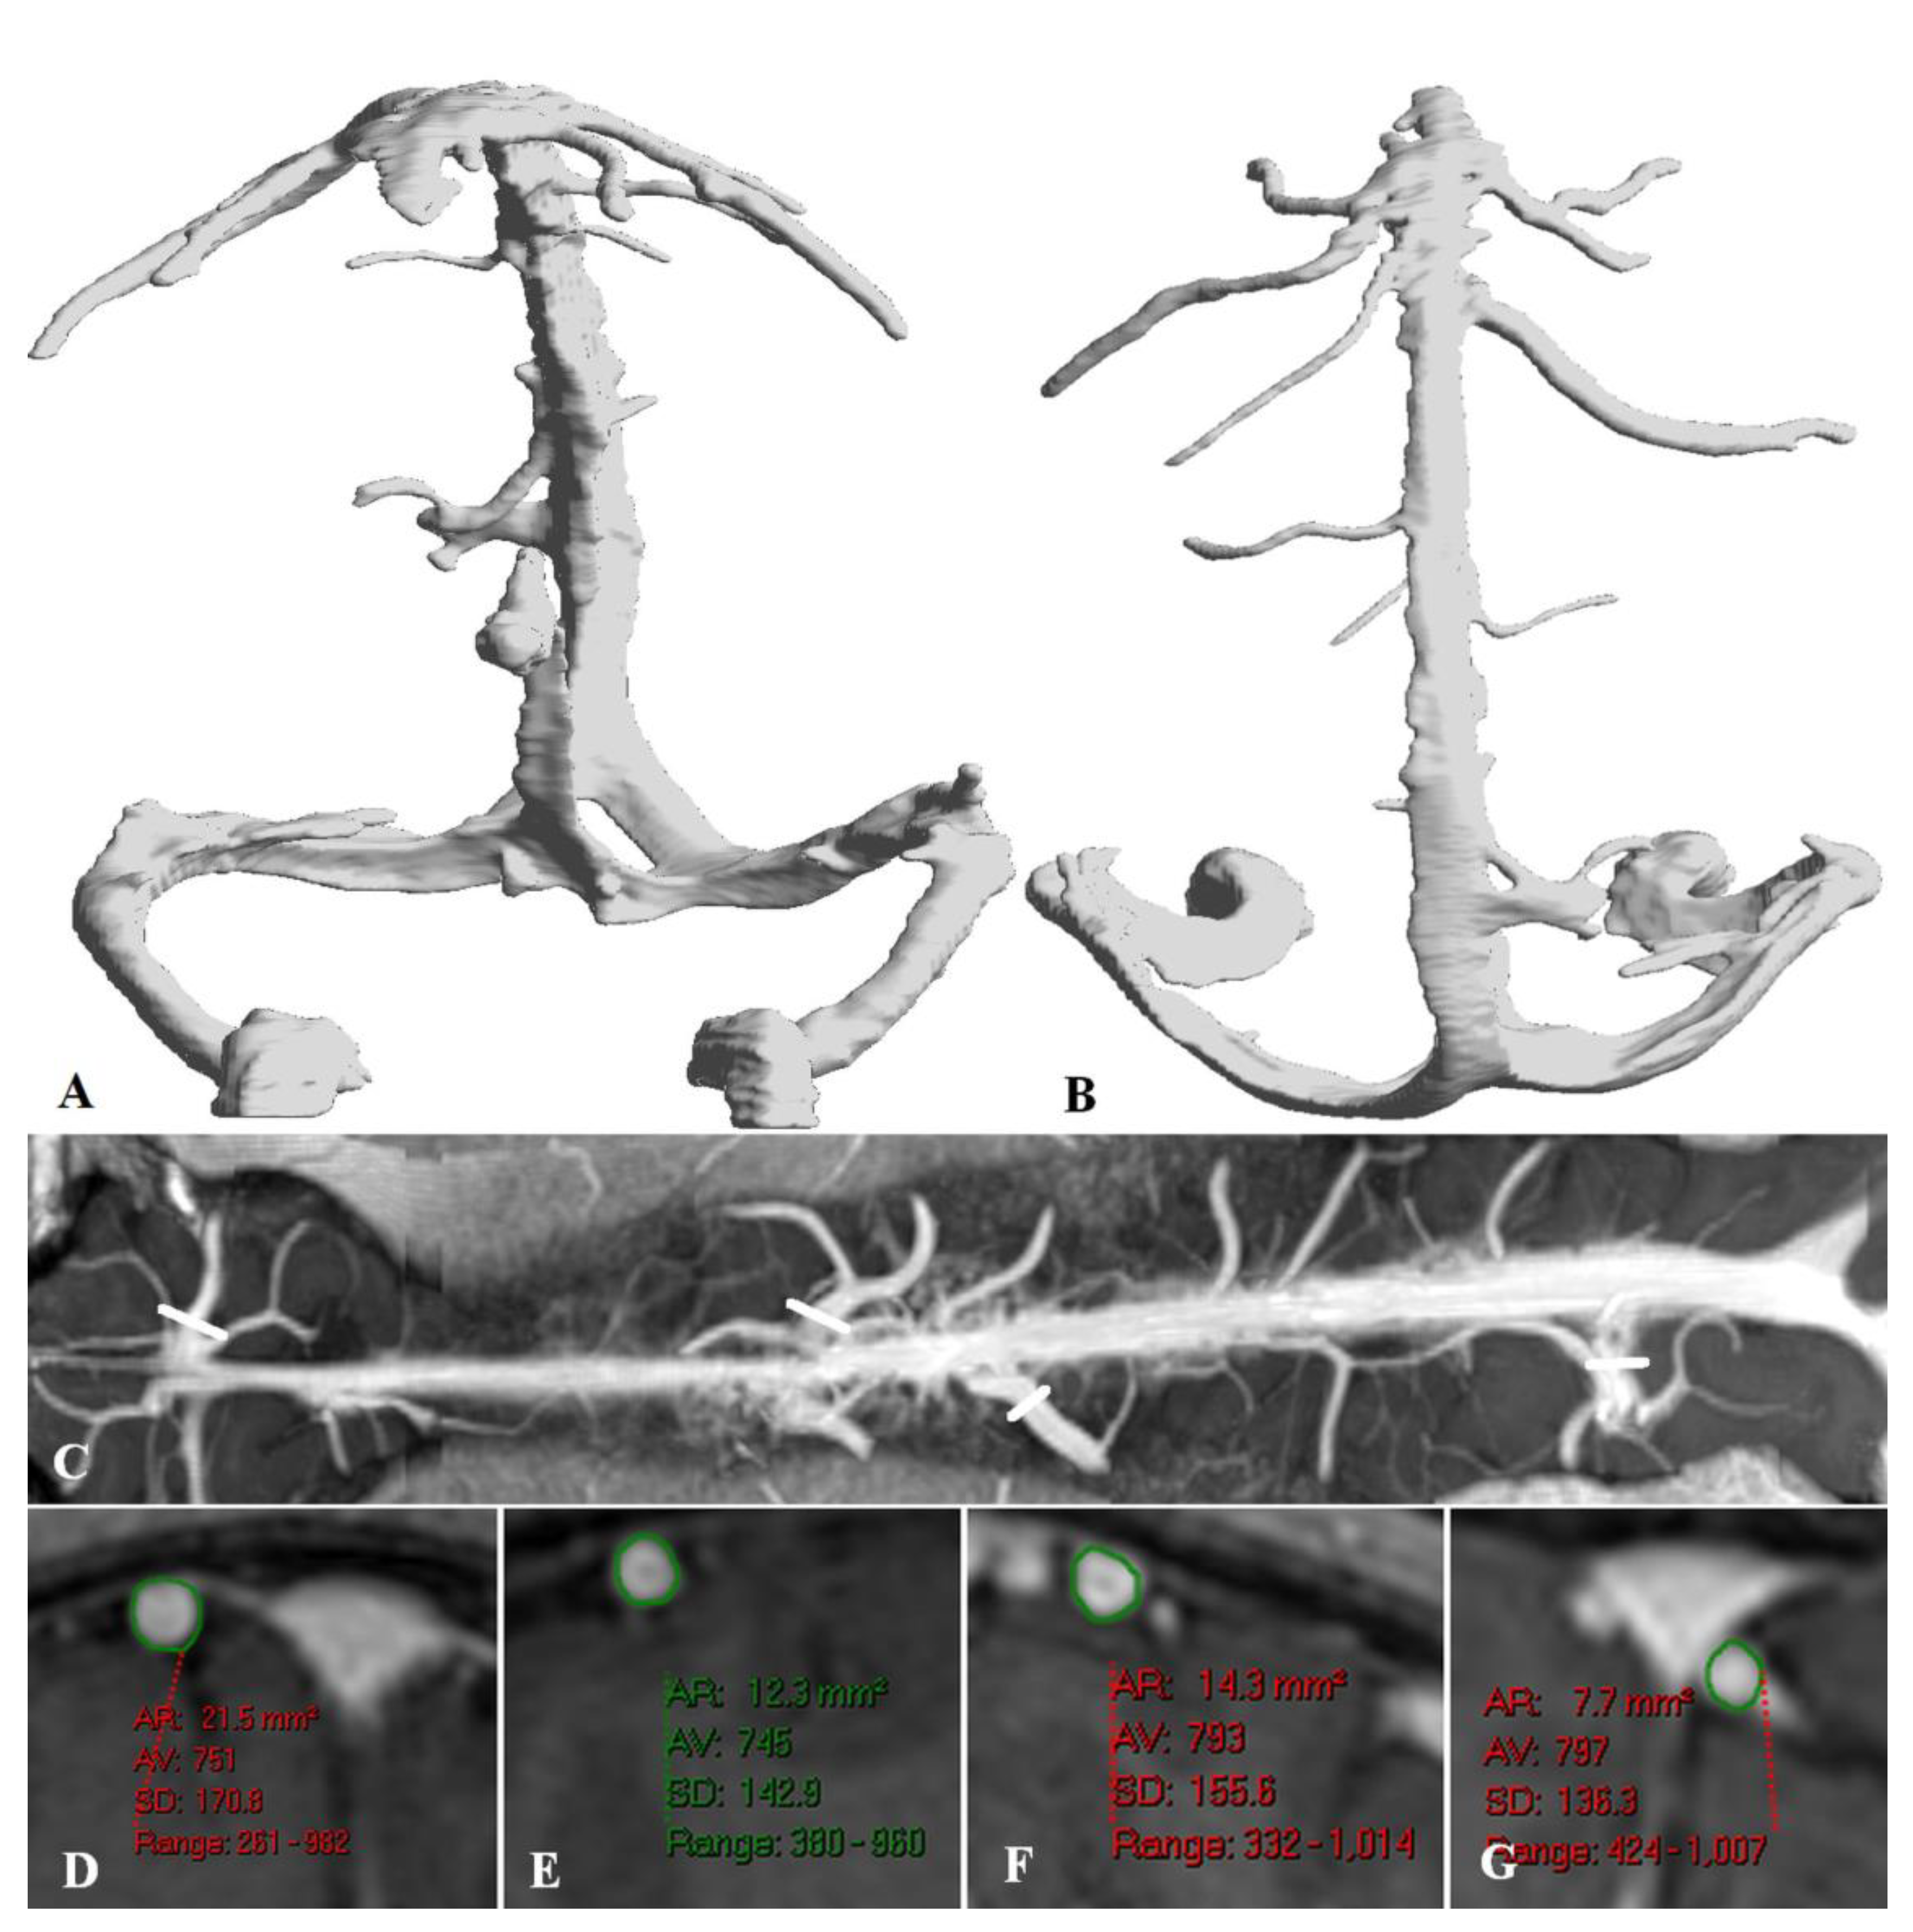

Bridging vein dilatation

Effect of elevated venous pressure on the brain.